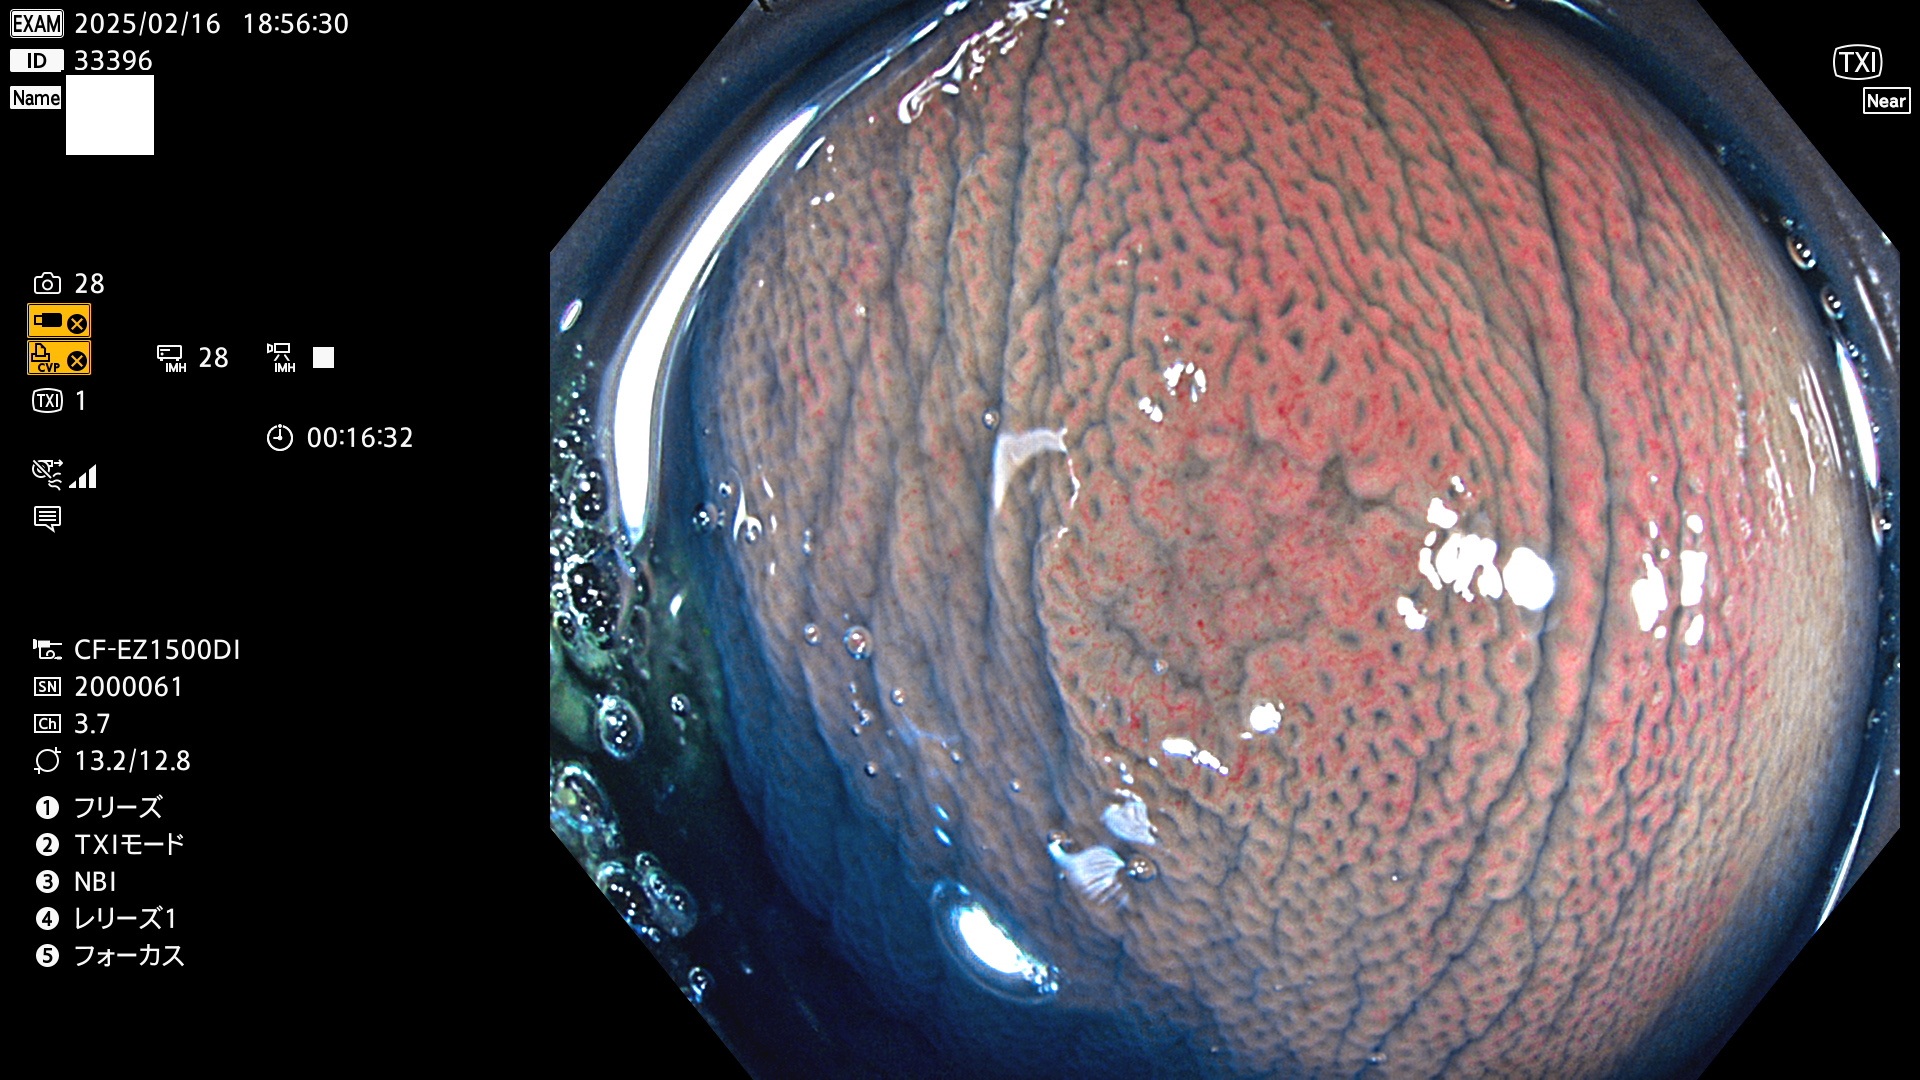

今週のUb、Uc型腺腫

完全に平坦な物をUb、陥凹している物をUcと呼びます。最も発見が難しく危険な病変です。

毎週の検査(木・金・土・日)に発見されたUb、Uc型・腺腫を、その週の日曜の夜にUPし1週間、提示します。

抽出の対象期間 2025年2月13日〜2月16日の4日間(48件の検査)8個 (8/48=16%)